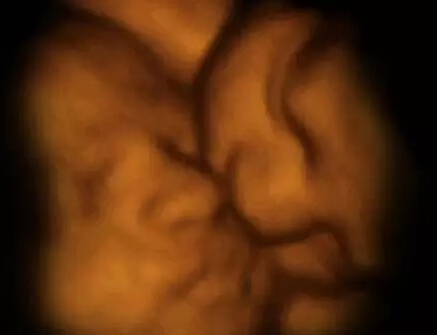

这张图见证了罕见的“双胎消失征”。图中居右的第3个胎盘是空的,这证明了多胞胎可能由于缺少营养而从子宫中消失。

研究中运用了4-D扫描图像,这些图像通过真实拍摄的3-D扫描图像合成。

科学家通过计算机生成图像获取了双胞胎、三胞胎和四胞胎如何在子宫中发育的新信息。

部新近完成的纪录片,追踪报道了这些珍贵真实的孕期过程,包括英国的胎四胞儿如何在大约6400万分之的几率下自然形成的过程。

这部名为《子宫里:双胞胎、三胞胎和四胞胎》的纪录片,通过计算机生成图像,将真实扫描数据制作成令人叹为观止的画面。